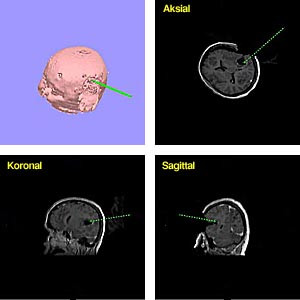

Ultralyd, MR og CT kan også gi tredimensjonale data (3D). Fortsatt er hastigheten ved 3D-avbildning så lav at systemet ikke kan benyttes interaktivt. Men 3D-funksjonen kan benyttes preoperativt i planleggingen av en intervensjon, intermitterende under en operasjon (fig 2) eller ved programmering av en robot (5, 6).